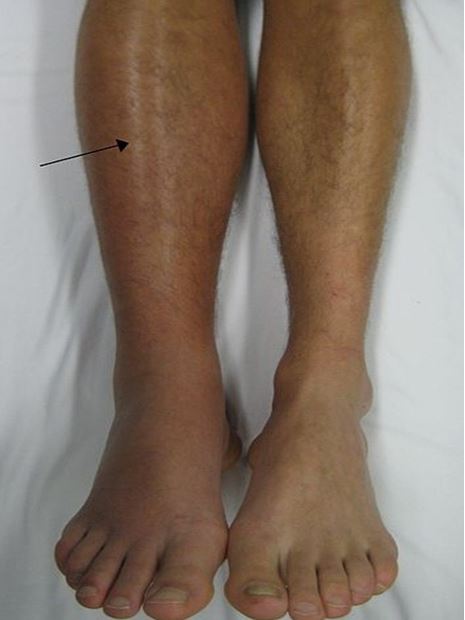

Đợt này, trước khi vào viện 7 ngày, bệnh nhân xuất hiện đau và sưng nề nhẹ vùng bắp chân trái, hạn chế vận động.

Khám lúc vào viện: bệnh nhân tỉnh; chân trái sưng nhẹ, hạn chế vận động, đầu chi hồng, không đau ngực, không khó thở. Có dấu hiệu Homans: đau khi gấp mặt mu của bàn chân vào cẳng chân. Mạch mu chân, mạch chày sau, mạch kheo chân trái bắt được.

Hiện tại: sau 1 tháng, bệnh nhân hết đau chân trái, không sốt, đi lại được

Trên hình ảnh siêu âm doppler mạch chi dưới bên trái hết hình ảnh huyết khối tĩnh mạch.

Các triệu chứng lâm sàng bao gồm: các bất thường xảy ra ở một bên chân trong trường hợp điển hình: đau chân, đau khi sờ vào bắp chân, có thể tìm thấy thừng tĩnh mạch (tư thế gập chân một nửa), dấu hiệu Homans: đau khi gấp mặt mu của bàn chân vào cẳng chân, tăng cảm giác nóng tại chỗ, tăng thể tích bắp chân (đo chu vi bắp chân và đùi mỗi ngày), Phù mắt cá chân, han chế vận động thụ động cẳng chân, giãn tĩnh mạch nông, thay đổi màu sắc chân.

Hình 4. Hình ảnh chân bệnh nhân bị khối tĩnh mạch sâu chi dưới bên phải.